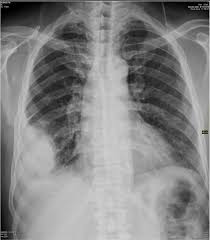

Black Spot On Kidney X Ray. X ray abdomen is simple cost effective and better choice to diagnose. A spot is not a standard descriptor it doesn t really mean anything from a radiology standpoint.

By cathey newton134465 4 posts last post over a year ago. Yesterday was my xray day because im having this back pain so they check if somethings wrong with my kidney. So im kind of worried still about that.

What was in the x ray report.

My doctor told me that my kidneys were ok but he was wondering about that black stuff. What might it be. By cathey newton134465 4 posts last post over a year ago. Rapid muscle tone loss.